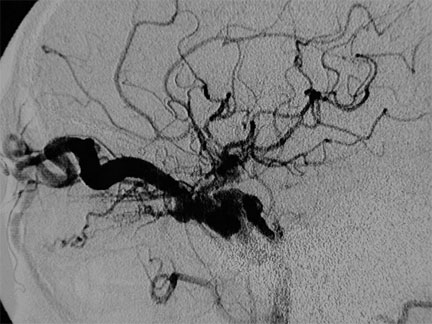

CASO 3 : Embolización de Fístula Carótidocavernosa espontánea en mujer joven con enrojecimiento visual y visión doble progresivas

Antes del tratamiento por embolización de fístula carótidocavernosa. Note la dilatación de la vena oftálmica responsable de la congestión ocular

Después del tratamiento por embolización de fístula carótidocavernosa. Note desconexión de la fístula con normalización anatómica y dinámica

Antes   Después